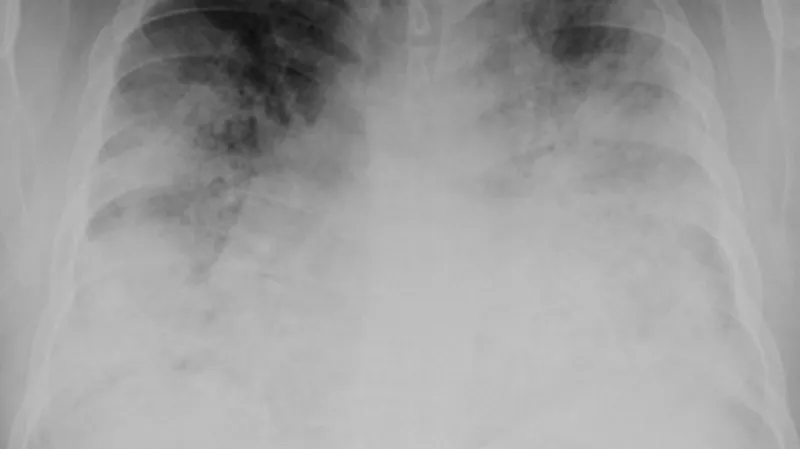

Bakterie legionelly se přirozeně vyskytují ve sladké vodě. Mohou se tak v malém množství dostat do nádrží s teplou vodou, vířivek nebo chladicích věží velkých klimatizačních zařízení. Když tam panují vhodné podmínky, může se tam namnožit. Obvykle se potom šíří vdechováním aerosolů, které bakterii obsahují.

Právě proto se tak špatně odhalovala ve filadelfském hotelu – šířila se tam z klimatizace a nakazila zřejmě hlavně ty, kdo byli nejdéle a současně nejblíž ke klimatizačním jednotkám.

Mezi rizikové faktory nákazy patří vyšší věk, kouření v minulosti, chronické plicní onemocnění a špatná funkce imunitního systému. Očkování proti této nemoci neexistuje, ale dá se jí dobře předcházet. Když jsou vodovodní a klimatizační systémy dobře udržované, je riziko namnožení poměrně malé.

Léčba legionářské nemoci spočívá v podávání antibiotik, mezi doporučené látky patří fluorochinolony, azitromycin nebo doxycyklin. Často je nutná hospitalizace, zejména u zranitelných osob. Úmrtnost se pohybuje i v těch nejvyspělejších zemích kolem deseti procent. Pokud ale nakažený trpí nějakými jinými vážnějšími nemocemi, může úmrtnost stoupnout až na 25 procent.